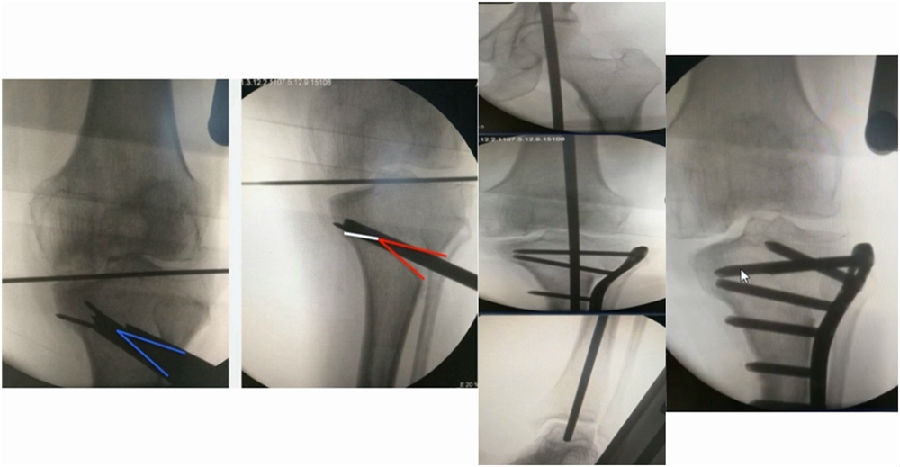

典型病例,女性,56岁,农民右膝内翻18度。

术前影像

术中影像

结合影像学来看,该患者单纯用闭合截骨或开放截骨,对肢体均有影响,所以决定采用混合型截骨。术中混合截骨旋转中心选在内外1/3处,先做闭合楔,然后顺势将开放楔敲开,达到术前设计的目标力线。术后随访力线达到要求。

术后X线